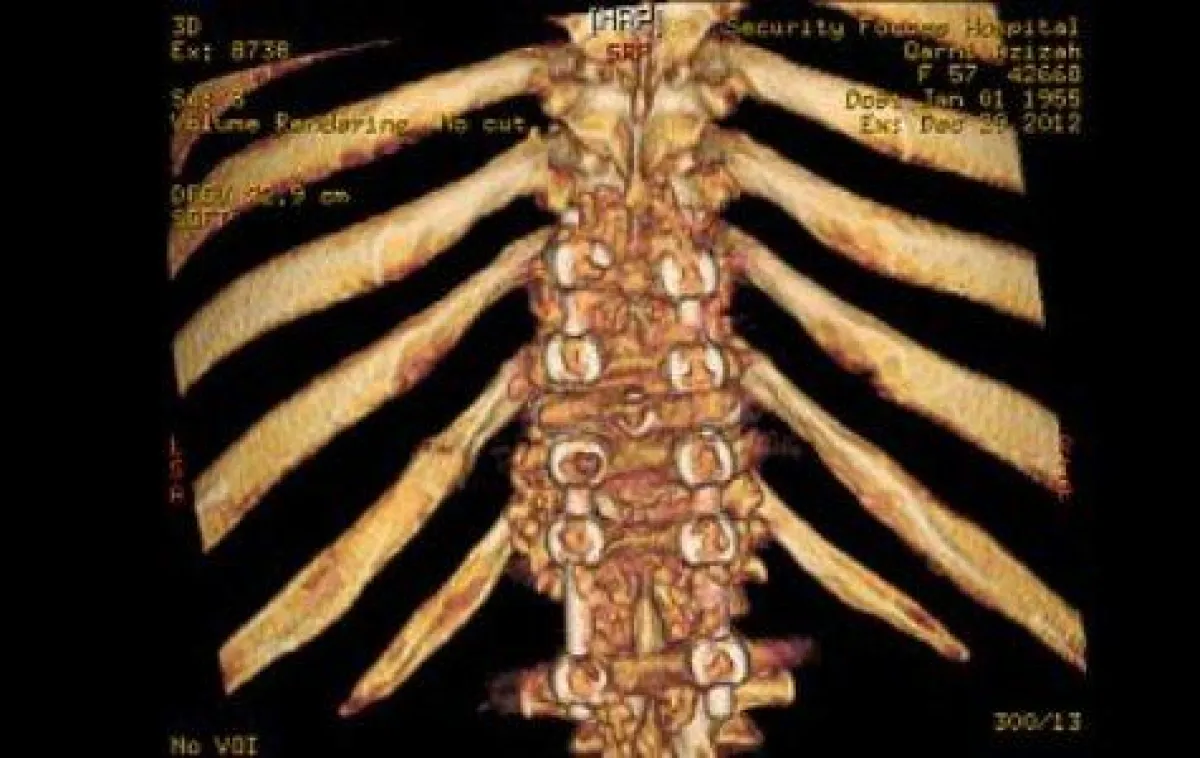

في أول عملية من نوعها تجرى في المملكة نجح فريق طبي بمستشفى قوى الأمن في الرياض بإنهاء معاناة سعودية تبلغ من العمر 57 عاماً مع الشلل التام في أطرافها السفلية وذلك بعد إجراء عملية جراحية لثبيت العمود الفقري باستخدام المسامير المثقبة وحقنها بالإسمنت الطبي، وكانت المريضة تعاني من كسر بالفقرة الظهرية الثانية عشرة نتيجة سقوطها في المنزل، وتعاني من هشاشة شديدة في العظام ومن عدة أمراض مزمنة منها: السكر، وتليف رئوي سابق، إضافة إلى روماتيزم شديد استدعى تناولها لمدة طويلة الكورتوزون الذي أدى إلى هشاشة العظم لديها بصفة عامة وضعفه وسهولة كسره، وبعد إجراء الفحوصات الإشعاعية تبين وجود كسر في العمود الفقري تسبب بالضغط على الحبل الشوكي ما أدى إلى شلل تام في الأطراف السفلية وعدم الاستطاعة على التحكم بالجهاز الهضمي والبولي، ومثل هذه العمليات تحتاج إلى تدخل جراحي سريع لرفع الضغط عن الحبل الشوكي وتثبيت العمود الفقري، ونتيجة لهشاشة العظام الشديدة التي تعاني منها المريضة وجد الفريق الطبي أنه من المستحيل استخدام الطرق التقليدية في تثبيت فقرات العمود الفقري، الأمر الذي يحتم عليهم إجراء عملية معقدة، إضافة إلى استخدام آلية حديثة في العلاج تتمثل في استخدام المسامير المثقبة التي تسمح بحقن الأسمنت العظمي (PMMA) داخل الفقرات منعاً لتهشمها كونها هشة، وللرفع من مستوى ثبات المسامير، وهي من العمليات الخطرة والتي في حال فشلها ستبقى المريضة تعاني من الشلل طوال حياتها، وتم تقديم شرح تفصيلي لأهل المريضة عن كل ما يتعلق بالعملية من حيث المدة ودرجة الخطورة والخطة أثناء العملية، وتمت موافقة أسرتها، وأجريت العملية الجراحية، والتي استغرقت ما يقارب 4 ساعات، حيث تم تثبيت فقرات العمود الفقري على 5 مستويات فقرية من الجانبين، ورفع الضغط عن الحبل الشوكي، وبعد الجراحة بثلاثة أيام بدأ تحسن مستوى القوى العضلية لدى المريضة ليصبح 5/5 في مفصل الكاحل، و3/5 في مفصل الركبة والورك، والآن تتمتع المريضة بوضع صحي جيد.